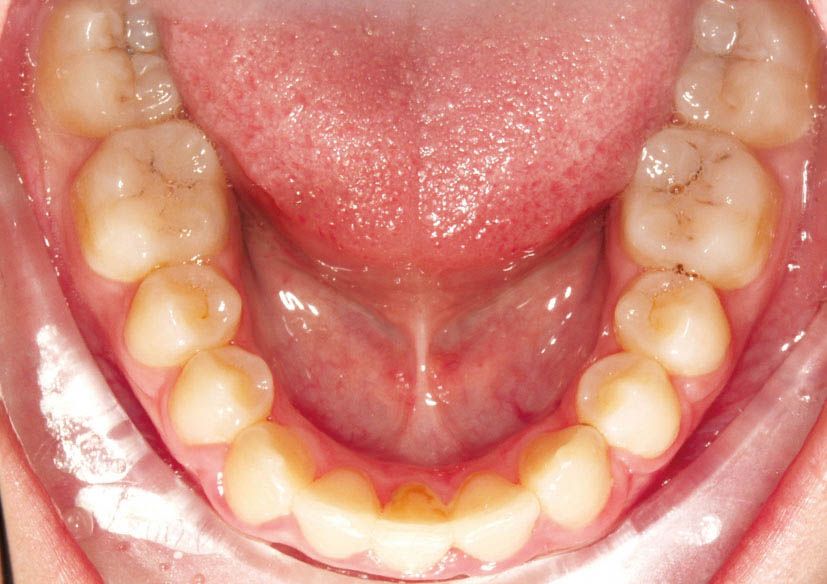

شکل 116-2: کشیدن یک انسیزور پایین و بستن فضا

از طرفی استریپ در این حد هم منجر به حساسیت انسیزورها میشود پس بهتر است در این گروه از بیماران، یکی از انسیزورهای پائین را بکشید (شکل 116-2). طبیعی است که میدلاین پائین در انتهای درمان Off خواهد شد (شکل 117-2) اما در زیبایی و لبخند اثر زیادی ندارد. میدلاین بالا در خنده اثر بسیار بیشتری نسبت به پائین دارد.